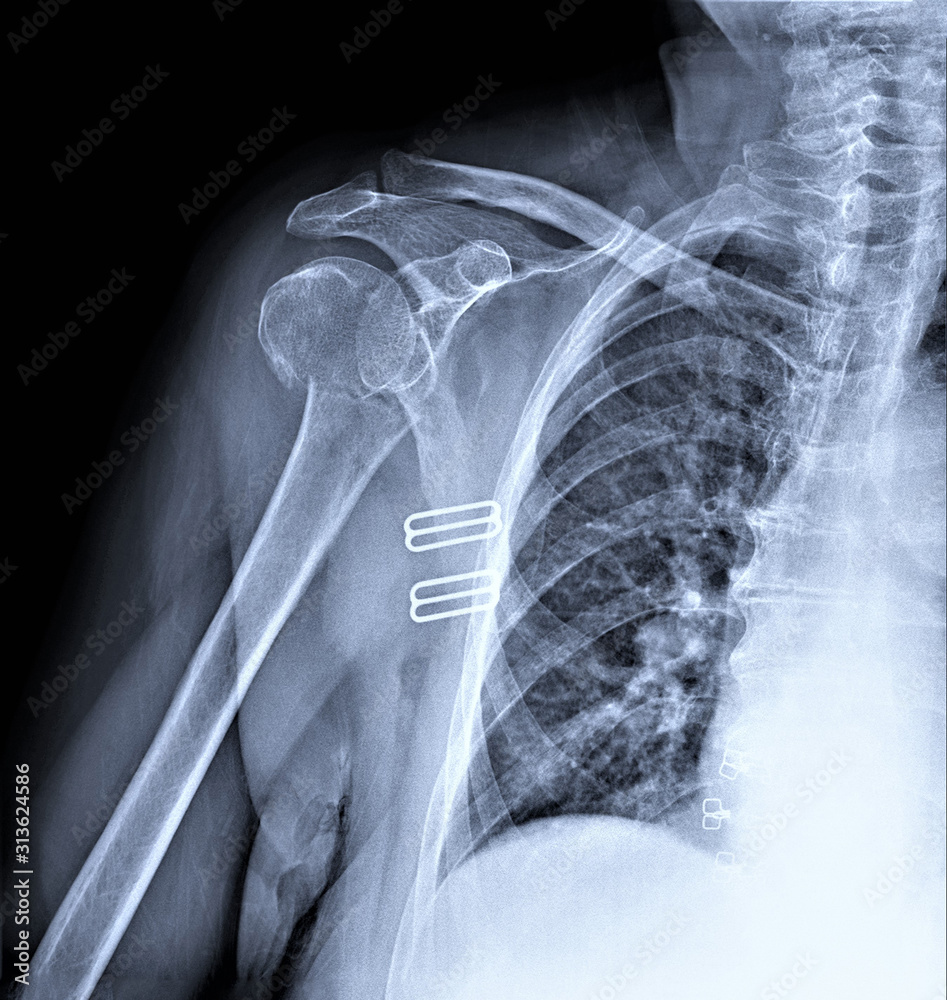

Fotka „radiography of the shoulder joint in direct projection with a Sports Injury Radiographer this article describes recent advances in quantitative imaging of musculoskeletal extremity sports injuries, citing the existing literature. a variety of imaging modalities are available to assess musculoskeletal sports injury, including radiography, ct, ultrasound, and mri. early referral for diagnostic imaging can clarify diagnosis and guide treatment. radiographs obtained early following acl injury most commonly demonstrate distention. Sports Injury Radiographer.

radiography of the shoulder joint in direct projection with a fracture Sports Injury Radiographer early referral for diagnostic imaging can clarify diagnosis and guide treatment. this article describes recent advances in quantitative imaging of musculoskeletal extremity sports injuries, citing the existing literature. Acl tears are one of the most. a variety of imaging modalities are available to assess musculoskeletal sports injury, including radiography, ct, ultrasound, and mri. radiographs obtained early. Sports Injury Radiographer.